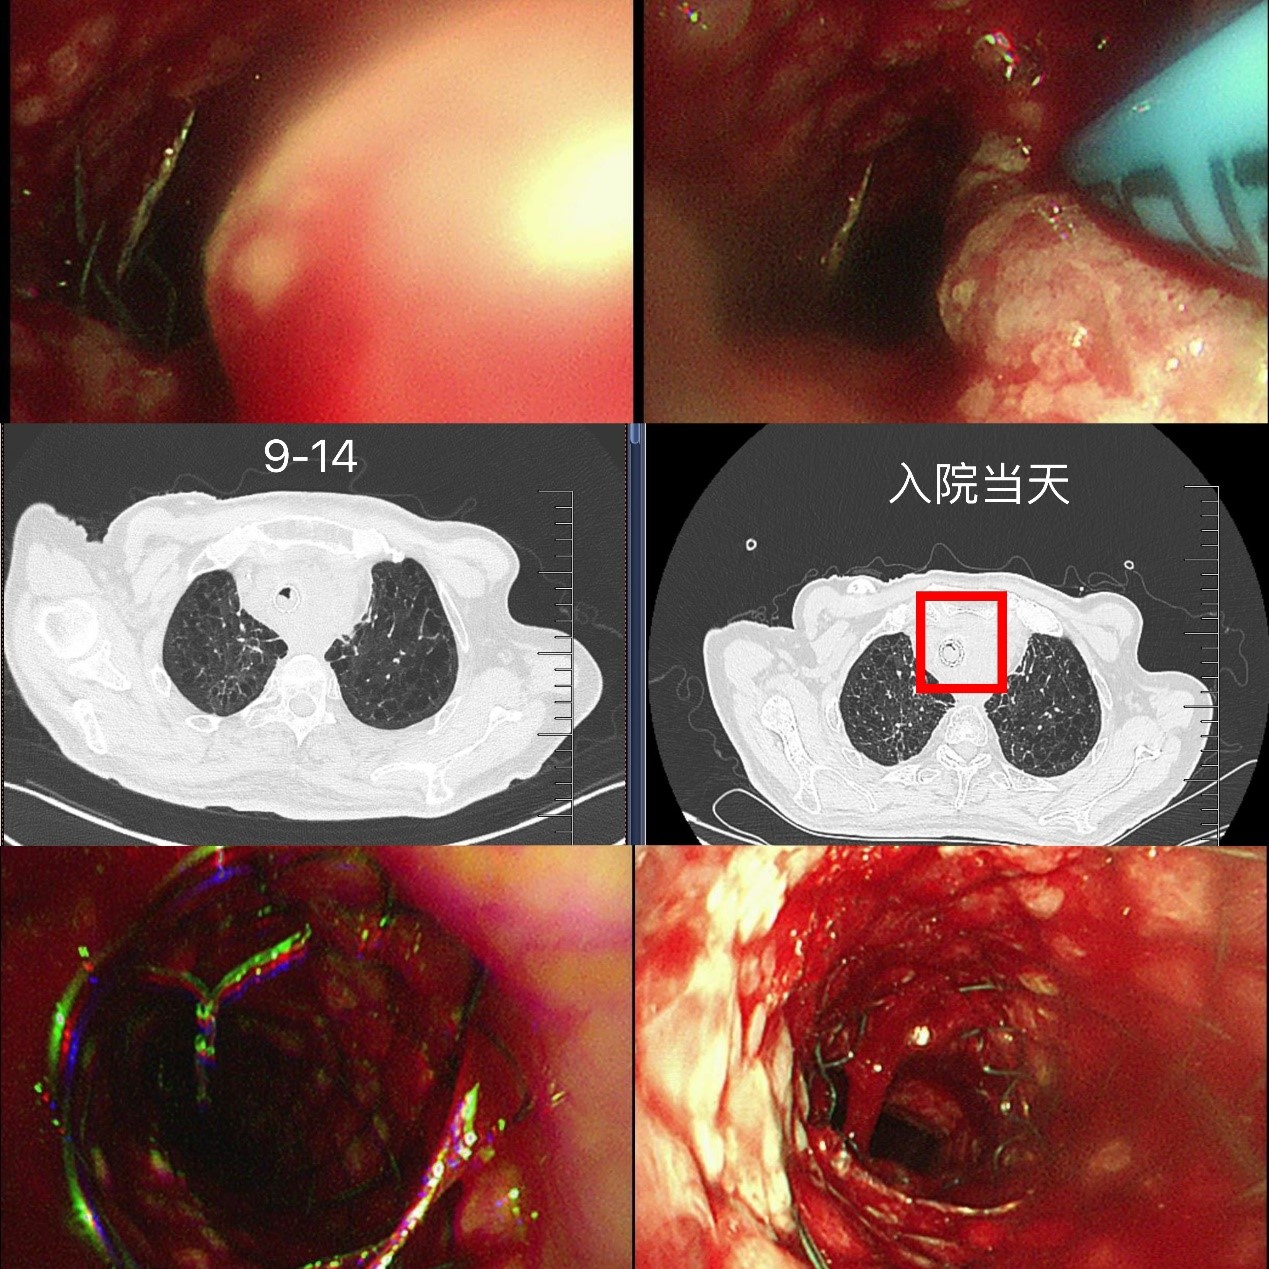

出院后,龚先生在苏大附四院肿瘤科接受了放疗(食管肿瘤灶及转移淋巴结)、替雷利珠单抗免疫治疗联合替吉奥口服化疗,8月复查时虽提示纵隔占位增大、局部压迫食管气管,但整体状态尚可。然而,9月中旬,他再次突发胸闷气喘,此时的龚先生虽神志清楚但精神极差,饮食睡眠受严重影响,不能平卧。龚先生被紧急送至我院急诊,收住入院,患者在无创呼吸机辅助下仍呼吸急促、呼吸窘迫。蒋军红主任团队为其紧急手术治疗,在手术室气管镜镜下景象触目惊心:原支架上端新生物已几乎完全阻塞气道,狭窄程度接近95%,且伴有活动后出血,随时可能因血块堵塞或缺氧危及生命。

蒋军红主任团队冷静制定策略:使用APC(氩等离子凝固术)对新生物进行局部消融,减少阻塞,稀释肾上腺素、冰盐水止血,随后快速的在原有支架腔内最狭窄部位,精准叠加置入一枚12×30mm金属裸支架。操作过程顺利,术后支架通畅度显著提升,远端管腔无明显狭窄,同步留取灌洗液送检明确感染与肿瘤情况。